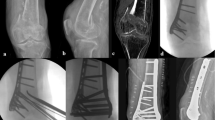

All patients were followed up for 12 to 48 months. The follow-up records of one patient of the double-plate group are shown in Figs 1–5 and those of one patient of the single plate group are shown in Figs 6 and 7. One patient in each group died one year and a half after the operation due to other causes. There were 58 patients and 60 cases of distal femoral fractures in total, of which one patient had bilateral distal femoral fractures both fixed by lateral plate and the other one with bilateral distal femoral fractures had a single plate on the right distal femur and double plates on the left. The age distribution of patients in the single-plate group and the double-plate group is shown in Table 1. There was no significant difference between the two groups (p = 0.330).

Inclusion criteria: Patients with distal femoral fractures treated with locking plate(s). Exclusion criteria: Patient with a decline of muscle strength of lower extremities. Anterior-Posterior and lateral plain film, computed tomography and 3D reconstruction of the fracture sites were performed to identify the fracture types.